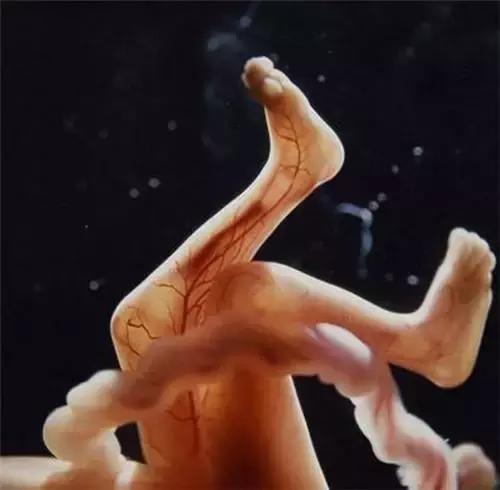

透过薄薄的皮肤,血管清晰可见